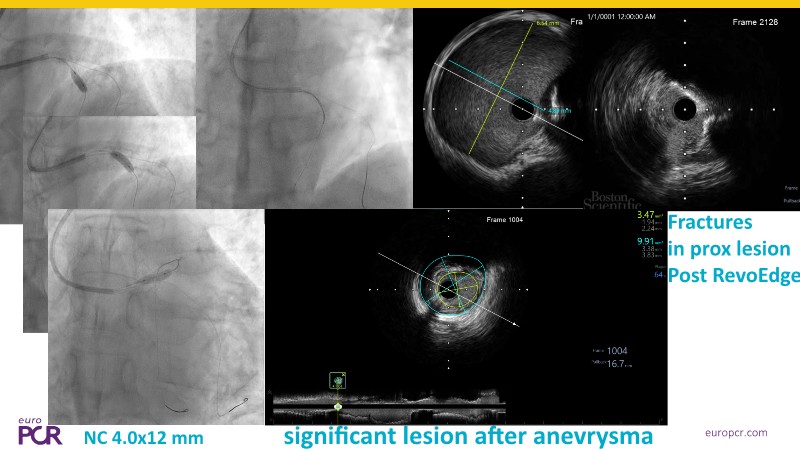

Discover how the next-generation RevoEdge high-pressure cutting balloon is transforming PCI with innovative design and proven clinical outcomes. This session presents a multicenter randomised trial and real-world case discussions, showcasing RevoEdge’s effectiveness in tackling resistant, complex lesions—including long, tortuous, and fibrotic cases. Learn practical tips, tricks, and intravascular imaging insights to optimize lesion preparation and improve patient outcomes. Don’t miss this opportunity to see how RevoEdge helps you cut through challenges and conquer PCI complexities.

- To explore the innovative design of RevoEdge: the next-generation high pressure cutting balloon

- To learn about the clinical benefits and tips and tricks of using RevoEdge high pressure cutting balloon in different types of complex lesions through case-based discussion